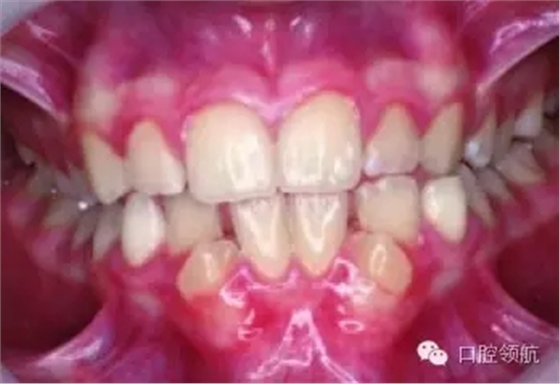

圖2.9中明顯的牙列異常有哪些?

雙側(cè)下頜側(cè)切牙和尖牙移位。

圖2.9

這種異常如何分級(jí)?

牙移位根據(jù)發(fā)生部位、牙齒類型和位置分級(jí)。這種雙側(cè)的移位分級(jí)為Mn.C.I2.

真性移位和假性移位之間的區(qū)別是什么?

真性移位是牙冠和牙根都發(fā)生移位;假性移位只有牙冠發(fā)生移位。